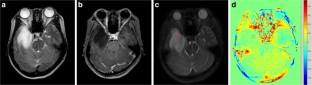

Fig. 1